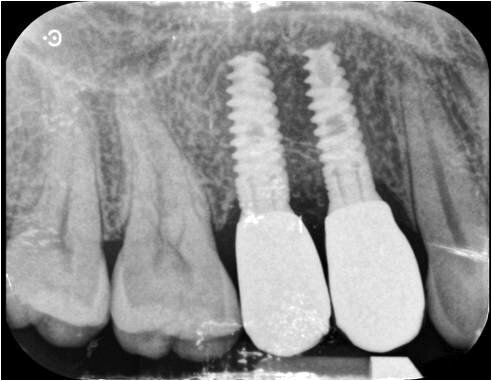

Fig. 7_Rx post-operatoria.

Fig. 12-14_Corone definitive e rx di controllo a due anni dalla chirurgia.